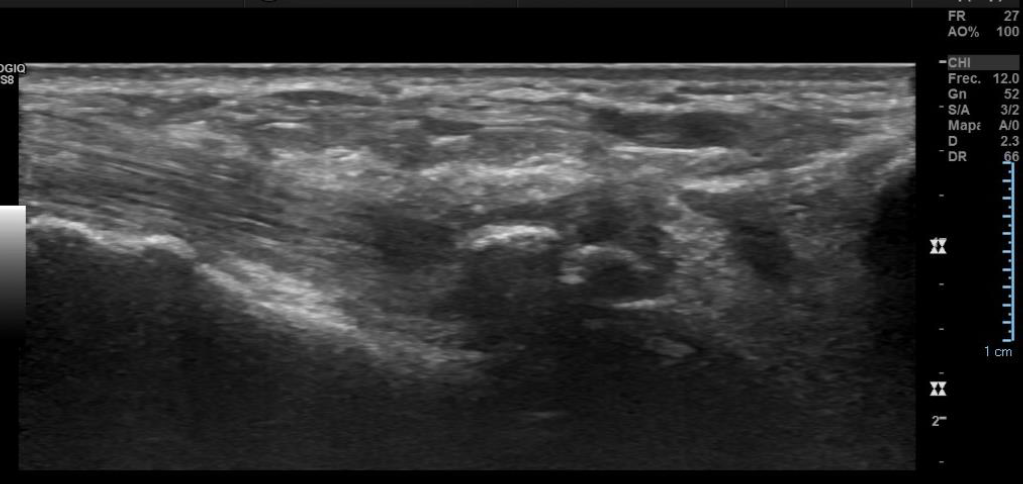

Hallazgos: Piel y tejido celular subcutáneo sin alteraciones significativas.

Engrosamiento y disminución de ecogenicidad del tendón peroneo largo en su región distal, sin desgarros.

Tendón peroneo corto, tibial anterior, extensor del hallux y extensor común de los ortejos de grosor y patrón fibrilar conservados.

Espacios articulares de amplitud normal y bordes regulares.

No hay signos de derrame articular.

Imagen con aspecto de os peroneo de contornos corticales irregulares, con cambios inflamatorios de las partes blandas adyacentes, pudiendo estar en relación a fractura a este nivel.

Impresión diagnóstica: Imagen con aspecto de os peroneo de contornos corticales irregulares, con cambios inflamatorios de las partes blandas adyacentes, pudiendo estar en relación a fractura a este nivel. Se sugiere evaluar con radiografía.

Tendinosis del peroneo largo en su región distal.